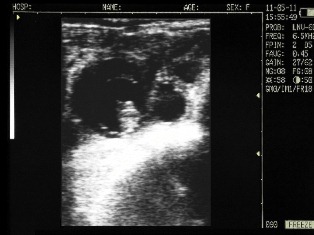

Ovary cows in mid-cycle

Corpus luteum in the ovary of the cow